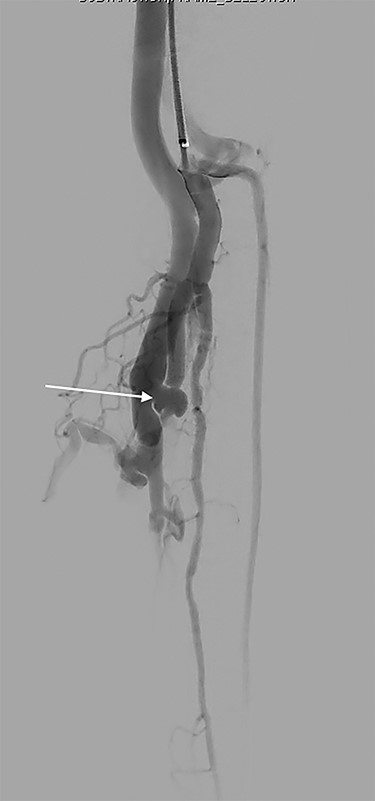

Formal angiogram was undertaken and posterior tibial AVF was confirmed (Fig. 1). Two Advanta V12 polytetrafluoroethylene covered balloon-expandable stents were placed in the posterior tibial artery (Merrimack, NH, USA): 5 × 22 mm distally and 6 × 22 mm proximally, resulting in successful exclusion of the fistula (Fig. 2).

Focused angiography pre-intervention with a catheter positioned at the origin of the tibio-peroneal trunk (TPT). Contrast flows into the TPT, through the AVF (arrow) and into the venous system.